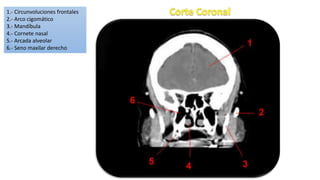

1.- Circunvoluciones frontales

2.- Arco cigomático

3.- Mandíbula

4.- Cornete nasal

5.- Arcada alveolar

6.- Seno maxilar derecho

1.- Circunvoluciones frontales 2.-Arco cigomático 3.- Mandíbula 4.- Cornete nasal 5.- Arcada alveolar 6.- Seno maxilar derecho